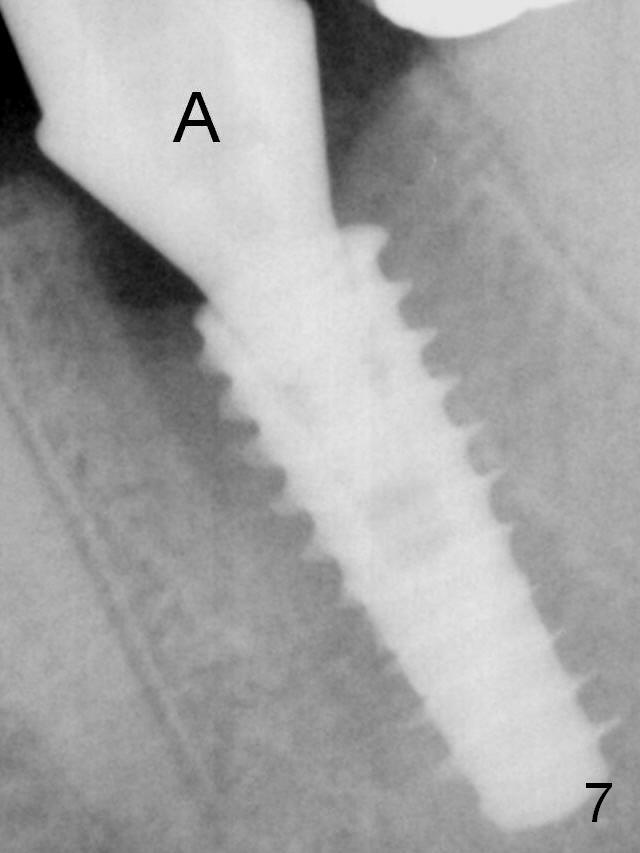

Insertion torque of a 5x13 mm implant is <20 Ncm (Fig.7). A 6.5x4(4) mm pair abutment is placed (A), apparently proper for restoration. Allograft is placed prior to immediate provisional. The patient complains of bad smell from the site 24 days postop. When the provisional is removed, the abutment is found to be mobile. When the latter is removed with local anesthesia, bone graft granules are attached to the socket above the lightly mobile implant. In fact the latter appears to be stable after a few turns by finger. A healing screw is placed; the socket is closed with collagen plug and 4-0 Chromic gut sutures. It appears that a larger implant should have been used to achieve higher torque. Two months later (3 months postop), the coronal end of the implant is partially exposed. A 5x4 mm healing abutment is placed. It appears that the implant is stable. The implant appears to have osteointegrated 4 months postop (Fig.11). Impression is taken. New bone has apparently covered the implant plateau 8 months postop (3 months post cementation (Fig.13 arrows)). The lower two-thirds of socket have disappeared.

Implant with Low Torque Last Next 1st Year Xin Wei, DDS, PhD, MS 1st edition 11/11/2016, last revision 09/03/2018